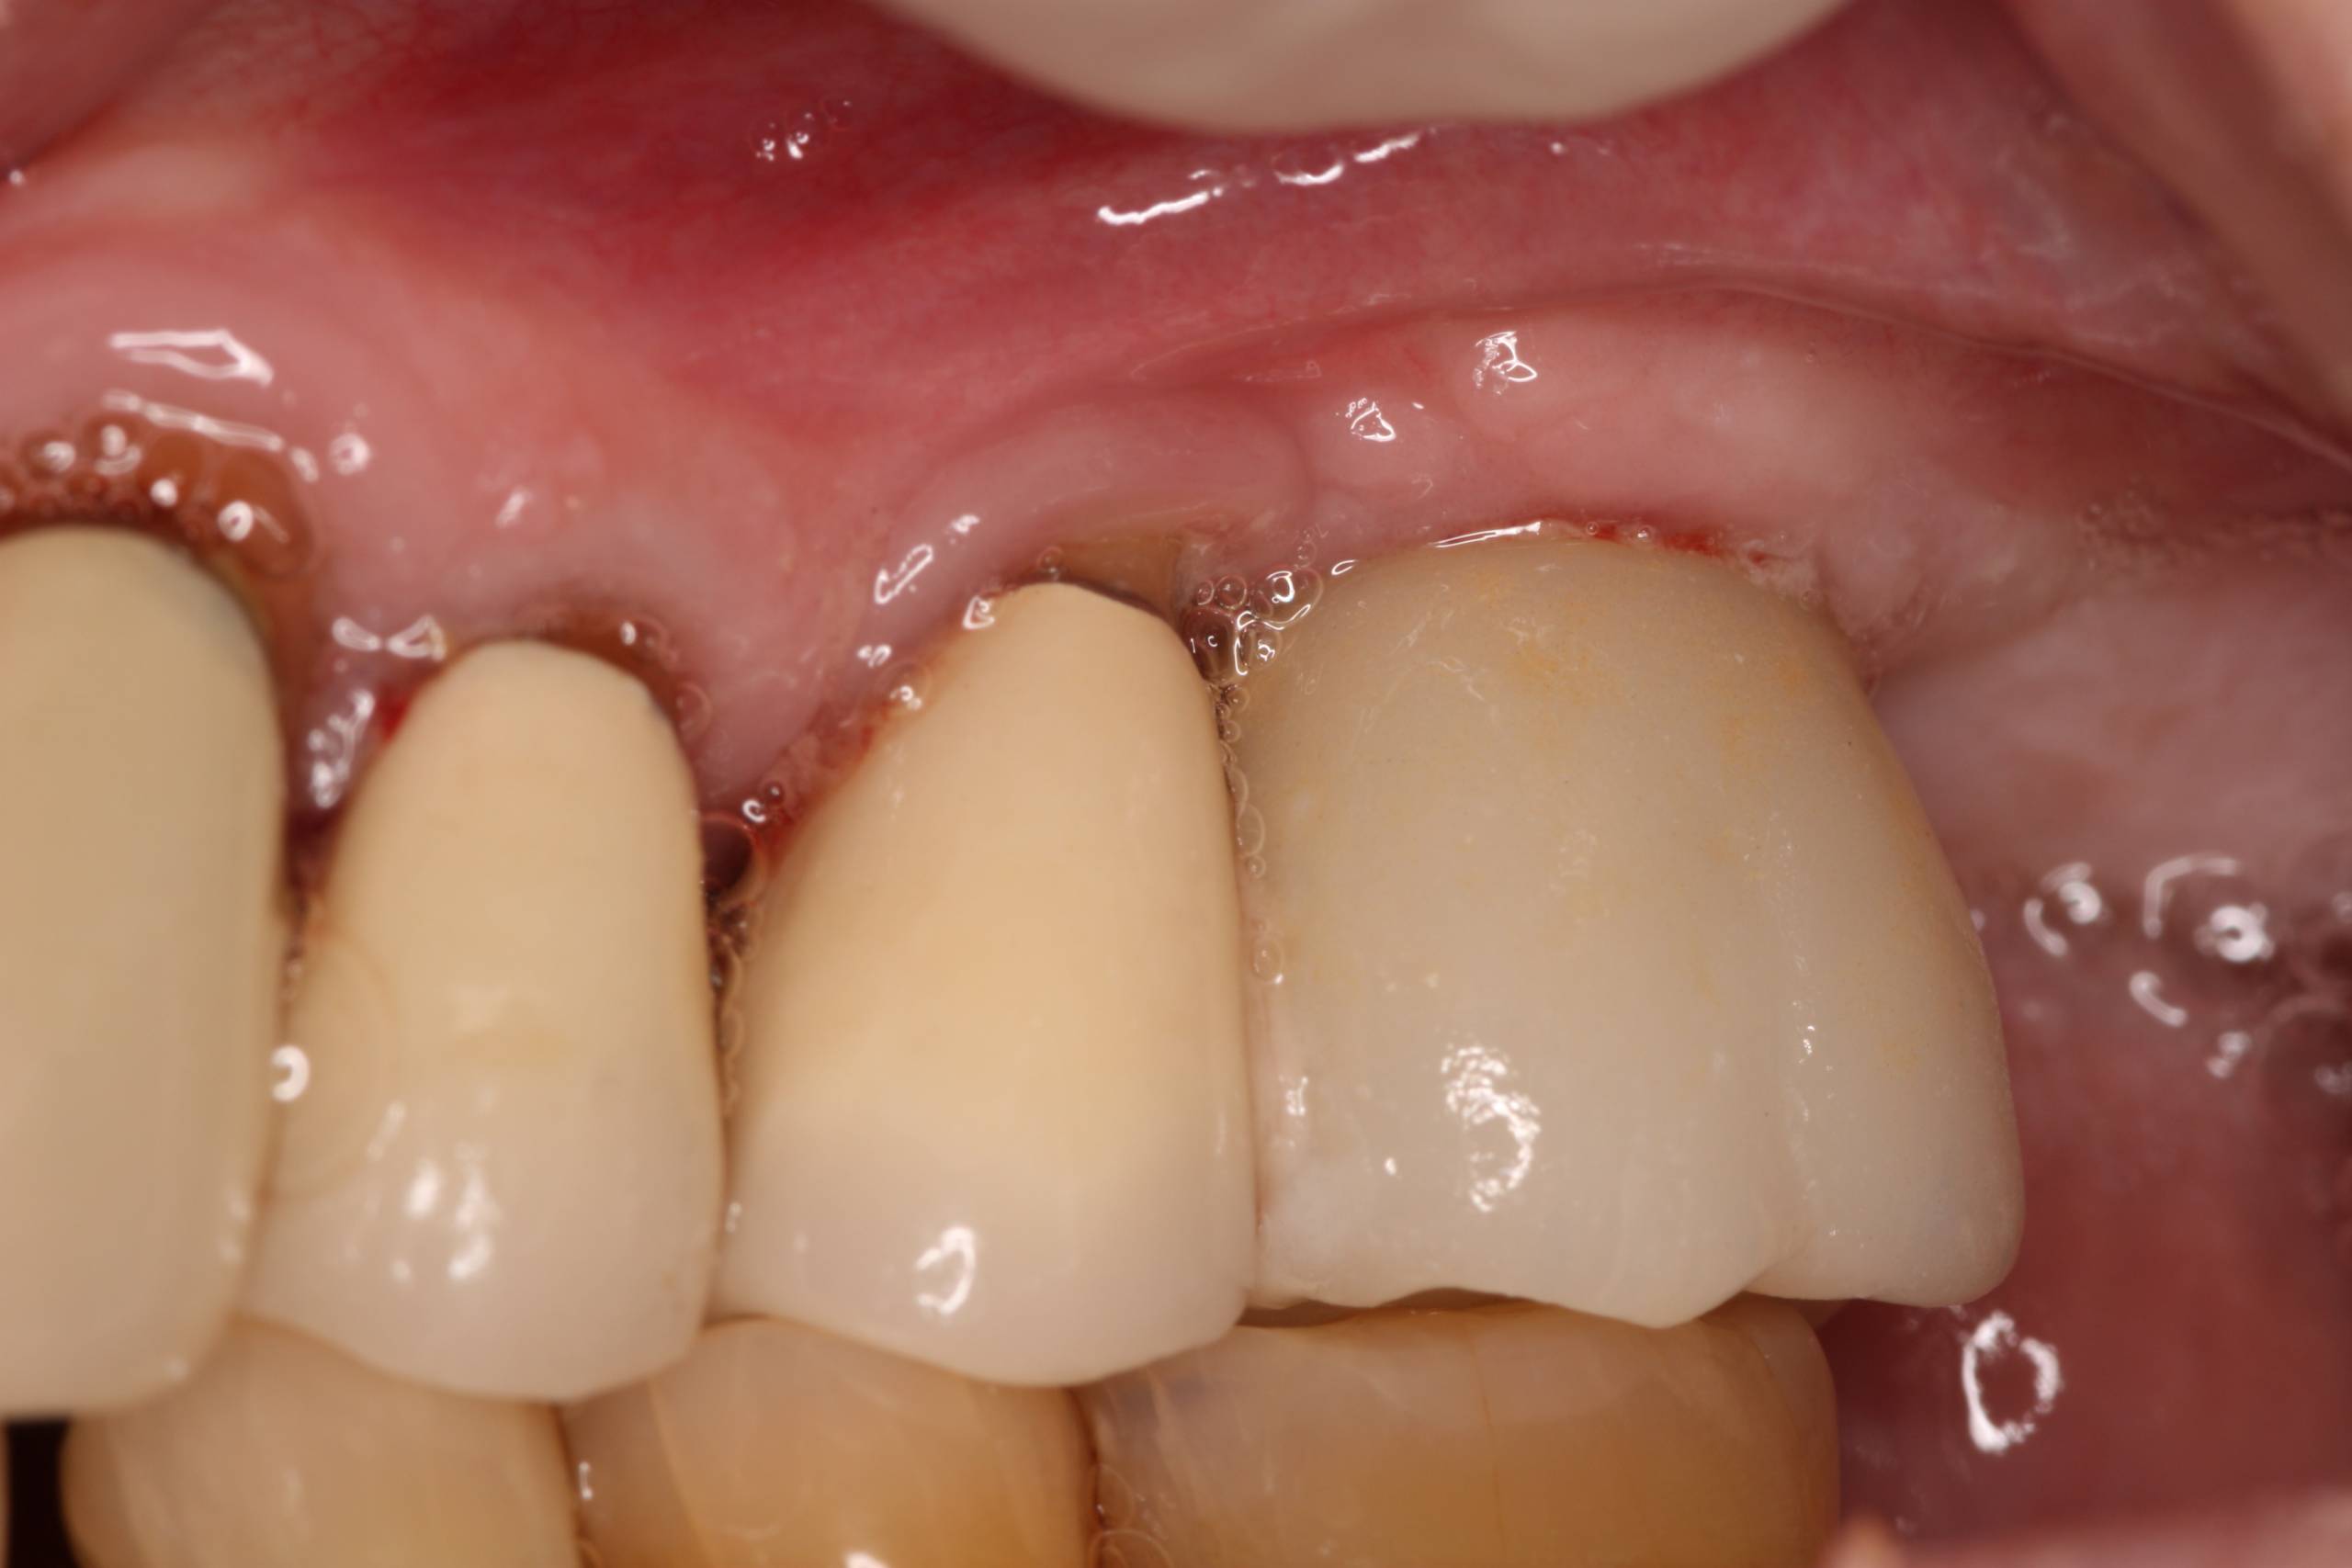

— покраснение мягких тканей, не исчезающее через 2-3 дня после операции;

Первые признаки аллергии могут проявляться покраснением, отеком десен, зудом или высыпаниями в области имплантата. Эти симптомы могут возникнуть в течение нескольких дней или недель после установки. Важно не игнорировать такие реакции, так как они могут указывать на непереносимость материалов. При появлении симптомов следует обратиться к стоматологу для обследования и, при необходимости, замены импланта. Врачи также советуют заранее обсудить возможные аллергические реакции на материалы, чтобы минимизировать риски.

Эксперты в области стоматологии и аллергологии подчеркивают, что первые признаки аллергии на зубные импланты могут проявляться в виде покраснения, отека десен, зуда или даже высыпаний в области рта. Эти симптомы могут возникнуть в течение нескольких дней или недель после установки импланта. Важно не игнорировать такие проявления, так как они могут указывать на непереносимость материалов, из которых изготовлены импланты, чаще всего это титан или его сплавы.

| Имплантат-ассоциированный мукозит | Воспаление слизистой оболочки вокруг импланта, покраснение, кровоточивость десен, боль | Обратиться к стоматологу для профессиональной чистки и оценки состояния импланта. Возможно назначение противовоспалительных препаратов. |

Если через 2-3 дня после операции покраснение, болезненность и отечность не уменьшаются, а неприятные ощущения усиливаются, обратитесь к стоматологу. Врач на основе внешних проявлений и жалоб определит проблему и дальнейшие действия.